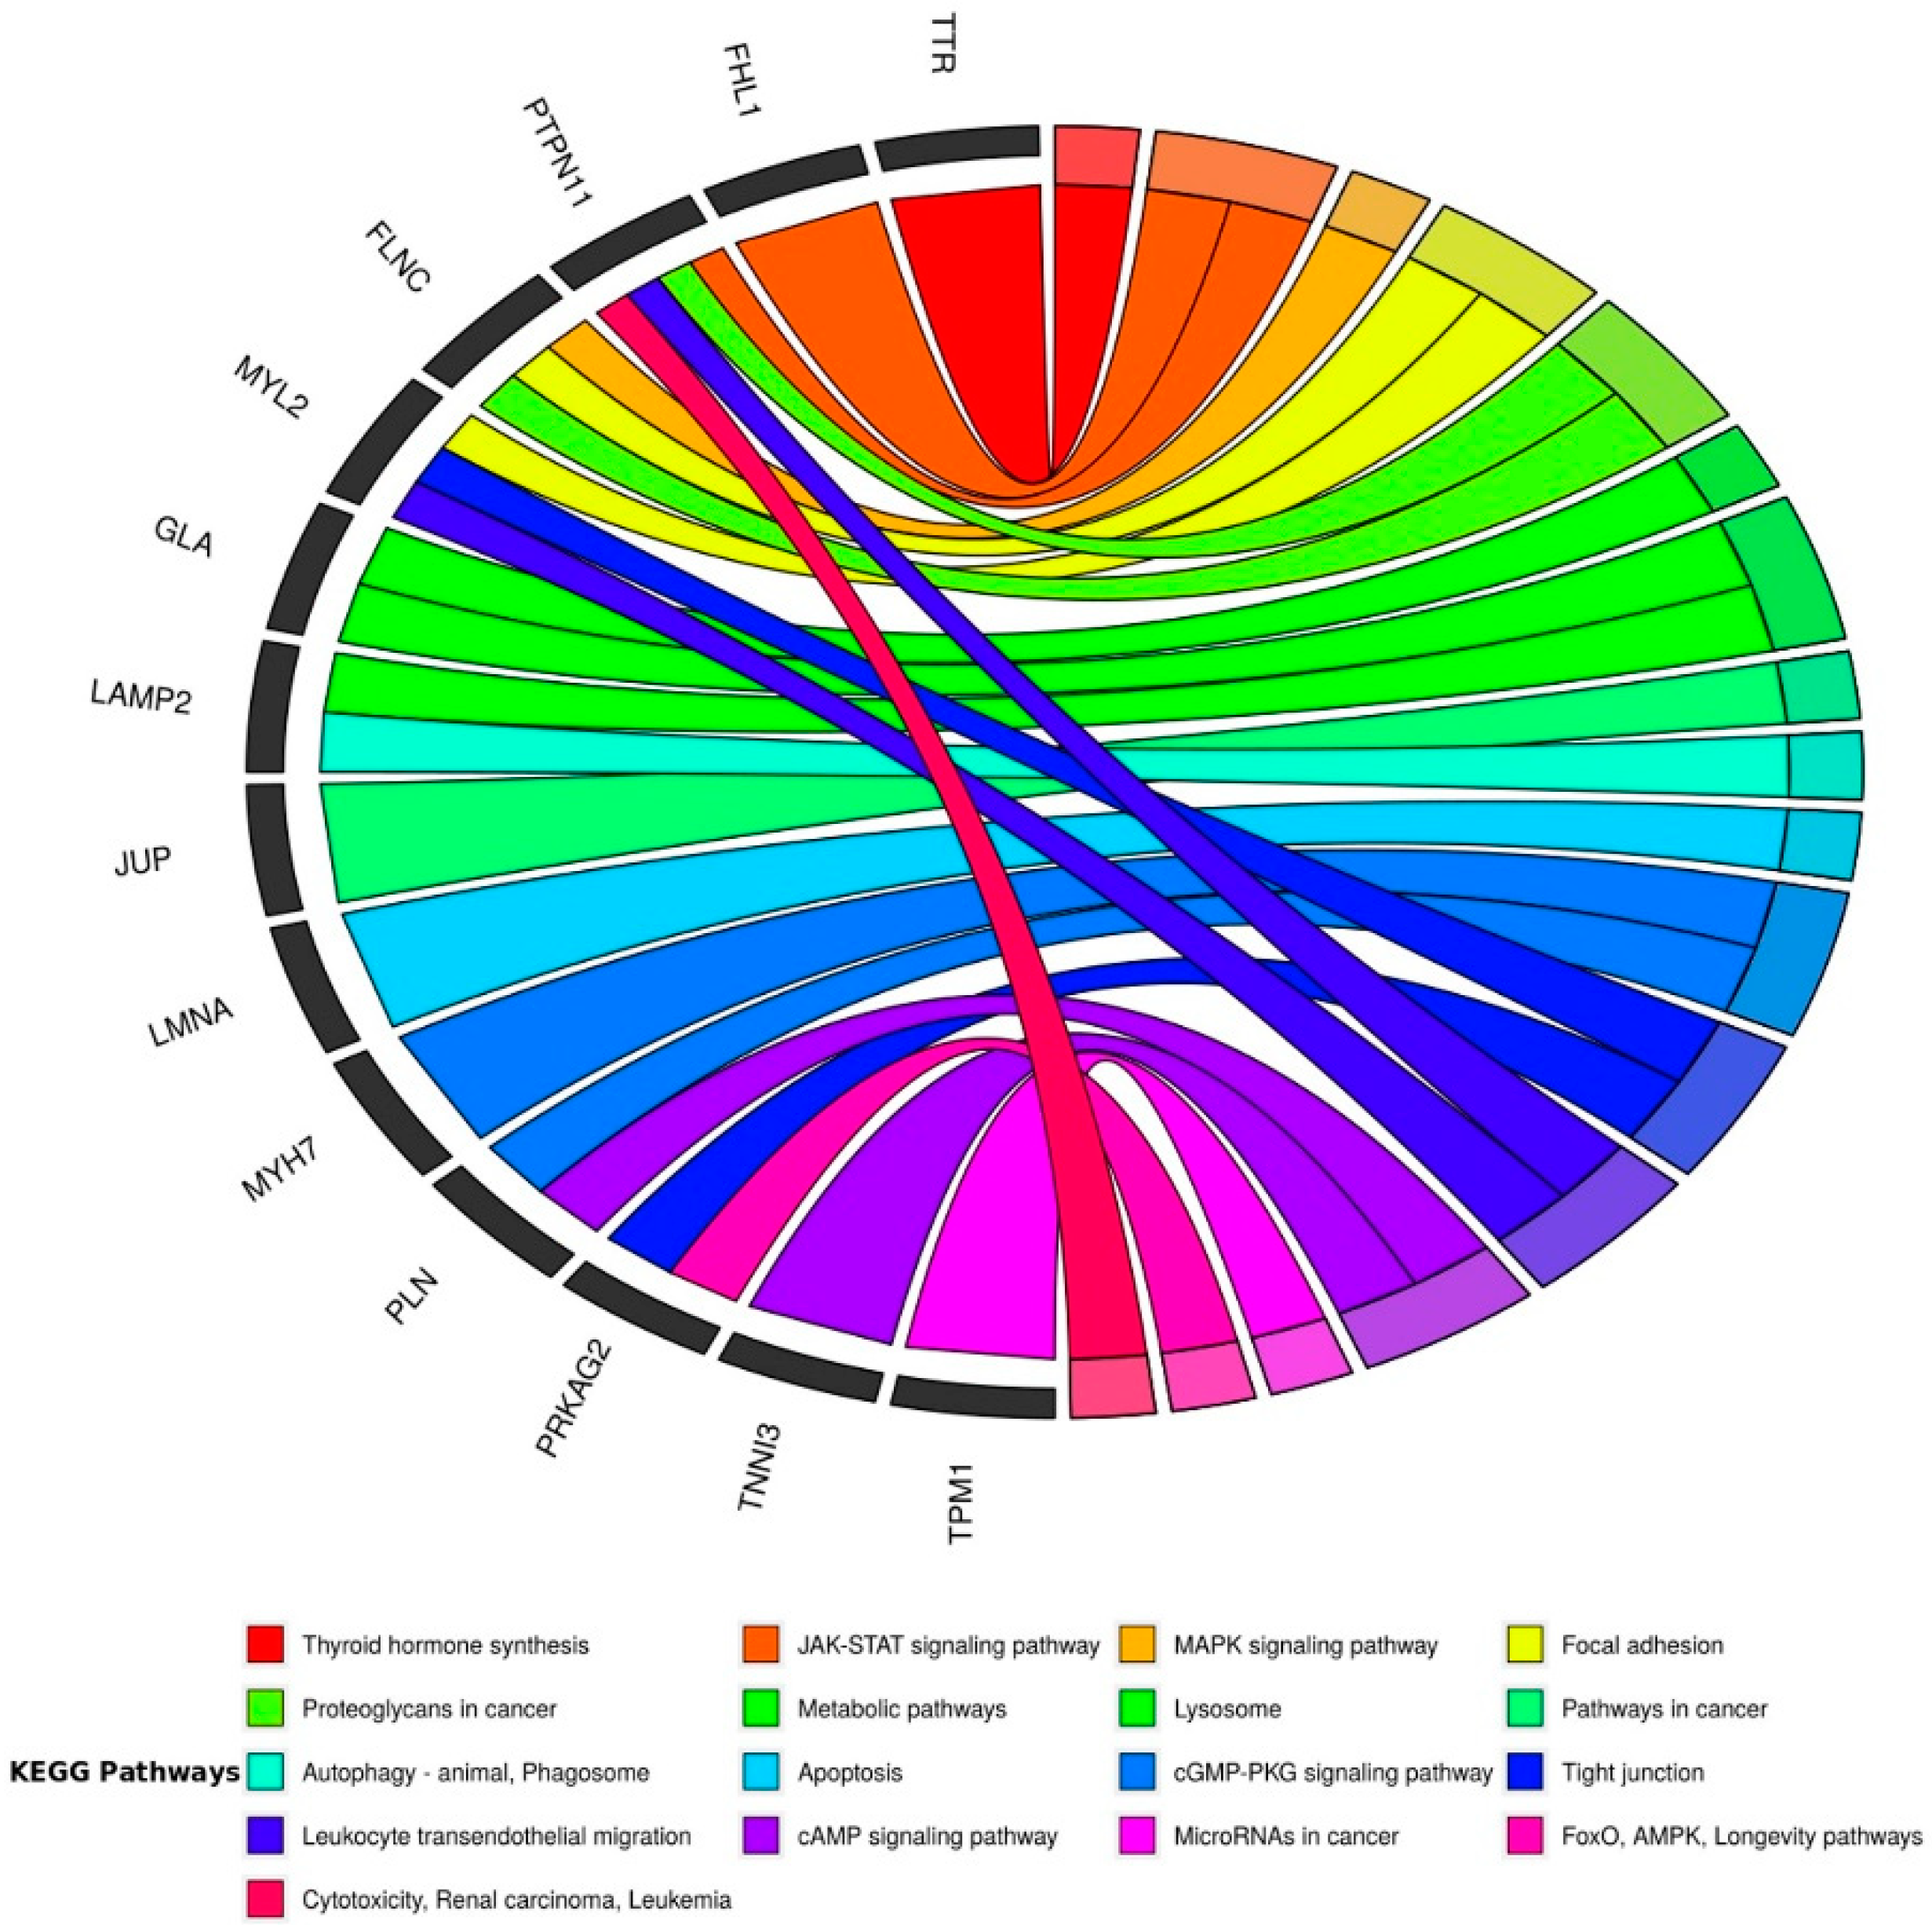

5. Predisposition to Cancer in Patients with Cardiac Associated Genetic Variants

5.1. Arrhythmogenic Cardiomyopathy: Disease of the Desmosome

5.2. Inherited Cardiac Disease and Cancer

5.3. Desmosome and Its Association with Invasiveness of Cancer Cells

- Kanehisa, M.; Goto, S. KEGG: Kyoto encyclopedia of genes and genomes. Nucleic Acids Res. 2000, 28, 27–30. [Google Scholar] [CrossRef]

- Leon, E.Z.; Carrasco-Navarro, U.; Fierro, F. NeVOmics: An enrichment tool for gene ontology and functional network analysis and visualization of data from OMICs technologies. Genes 2018, 9, 569. [Google Scholar] [CrossRef] [Green Version]

- Walter, W.; Sánchez-Cabo, F.; Ricote, M. GOplot: An R package for visually combining expression data with functional analysis. Bioinformatics 2015, 31, 2912–2914. [Google Scholar] [CrossRef]